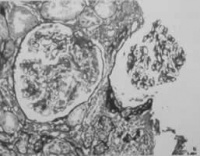

肺结核病变侵蚀血管壁而引起出血,出血量可因损伤血管的大小及深浅程度而不等。当空洞壁上血管瘤(小动脉瘤)破裂时,可出现大量的咯血,甚至发生窒息休克或死亡。

2.血管壁侵蚀,破裂 肺部慢性感染使血管壁弹性纤维受损,局部形成小动脉血管瘤在剧烈咳嗽或动作时血管瘤破裂而大量出血,常造成窒息,突然死亡此种血管瘤多见于空洞性肺结核。